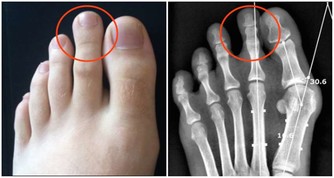

這是一種影響所有年齡段人群的長期病症。最常見的類型是骨關節炎,由關節內光滑的軟骨逐漸磨損引起的。其症狀包括關節疼痛、壓痛、僵硬,並且在受影響的關節上皮膚會出現紅腫。